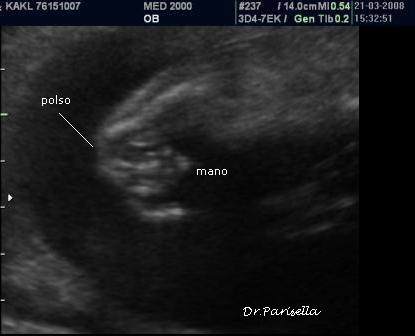

2) artrogriposi caratterizzata principalmente da contratture in flessione;